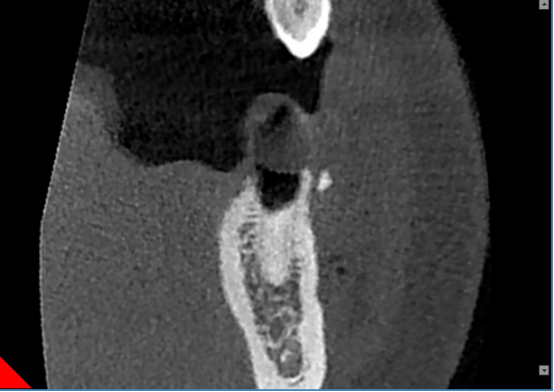

残根

颌面外科扫描能精确展示特定解剖特点,如囊肿或牙断裂,深度牙根形状和倾斜度。